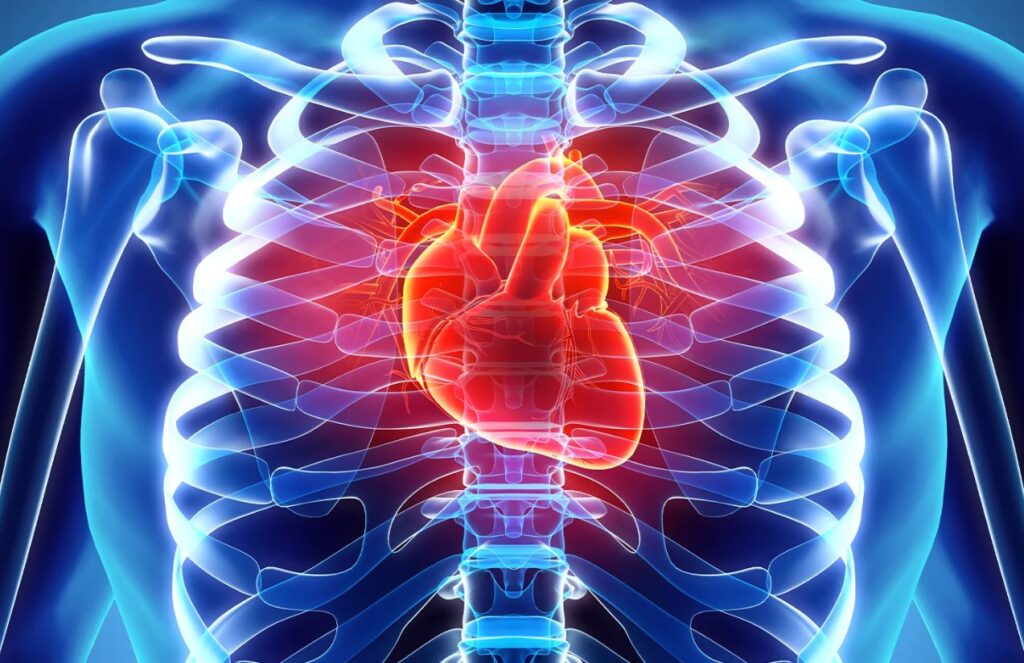

Science is once again highlighting something often underestimated: what we eat can make the difference between a healthy life and a high risk of cardiovascular disease. New research has identified three key pillars in the diet that help protect the heart, along with one factor that can be especially dangerous if not controlled.

First is the consumption of whole grains, which are associated with a lower risk of heart disease thanks to their high fiber content. Second, fruits and vegetables, especially leafy greens and those rich in vitamin C, play a fundamental role in strengthening arteries and providing essential antioxidants. Finally, maintaining a diet rich in natural, minimally processed foods enhances these benefits and helps reduce cardiovascular mortality.

However, there is one clear enemy: excess sodium. Adding too much salt to meals can significantly increase the risk of heart problems and even premature death.

Experts also recommend avoiding ultra-processed foods, sugary drinks, and processed meats, as they are directly linked to cardiovascular issues.

What is the key to taking care of your heart according to science?

Maintaining a diet rich in natural foods like fruits, vegetables, and whole grains, while limiting salt and processed products. The conclusion is clear: small changes in diet can have a huge impact on heart health in the long term.